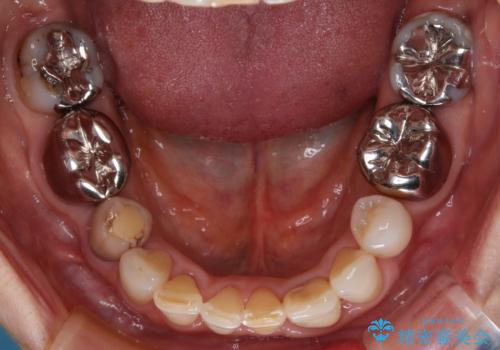

奥歯の目立つ銀歯をセラミックに オールセラミッククラウン治療